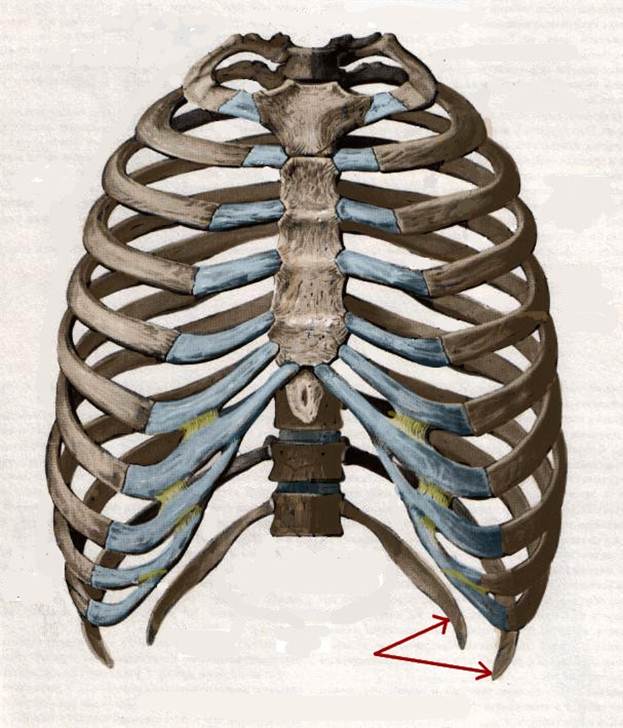

S: Стрелки указывают на сostae fluctuantes (латинский язык).